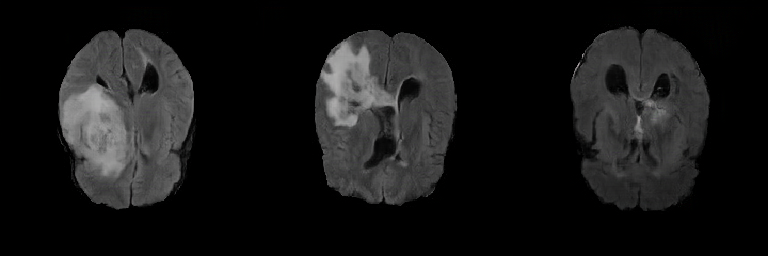

Generated Images Figure 5 shows the generated brain tumor FLAIR samples from -GAN-GP, PGGAN, and PGGAN-SSIM in AXI. The generated samples from all models look realistic and are close to the real images, where the white areas (Gliomas area) are concentrated and unified, indicating the training stability with gradient penalty. However, the samples from -GAN-GP are blurry, and the detailed brain features disappear since the loss of image information becomes serious when the image resolution increases in -GAN-GP. The generated samples from PGGAN and PGGAN-SSIM have clear and realistic brain features (FLAIR texture and tumor appearance) with diversity, which illustrates that PGGAN architecture is a well-suited model to generate brain MR images.